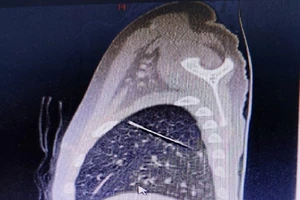

Giật mình khi đang ăn, người đàn ông bị mảnh xương cá diêu hồng cắm vào dây thanh quản 20/04/2022 13:53